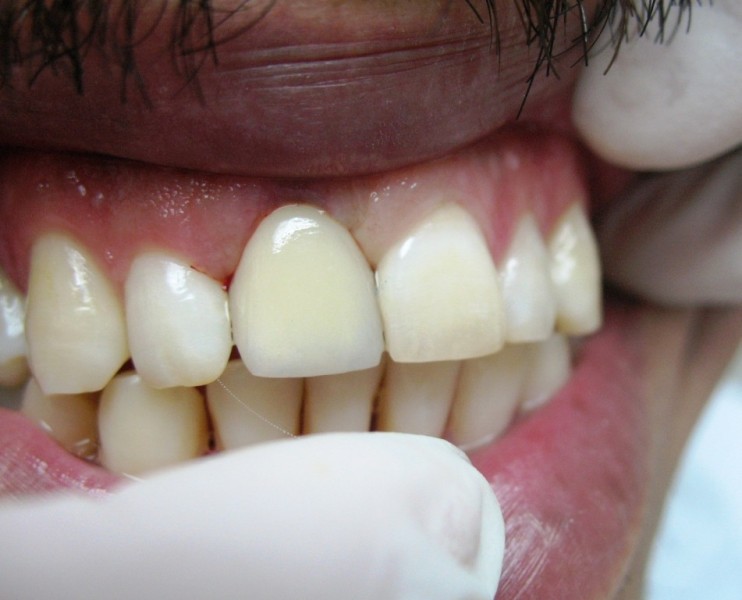

A Case with a Fractured Central Incisor